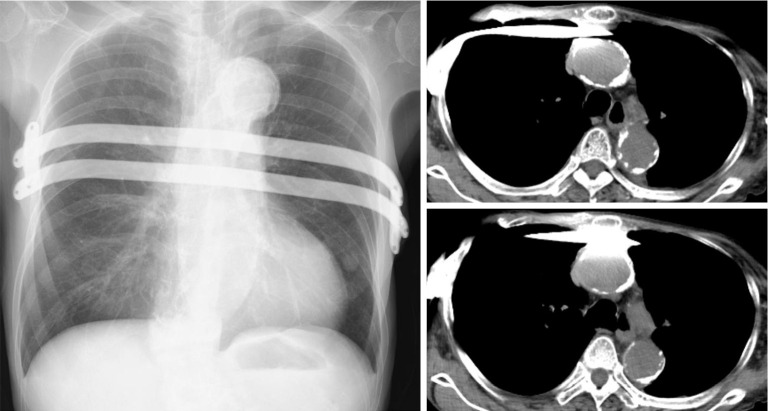

Case description: A 72-year-old woman presented to the emergency department with ventricular fibrillation caused by acute myocardial infarction. The patient underwent cardiac catheterization and coronary artery stenting following cardiopulmonary resuscitation (CPR). The patient was referred to Fukaya Red Cross Hospital owing to dyspnea caused by a flail chest following CPR. Being an elderly woman, the supporting tissues of the thorax had weakened, and she had a pronounced flail chest, a labored breathing pattern, and severe respiratory distress. Although there is the disadvantage that cardiac massage would become difficult, the cardiologist determined that cardiac function had stabilized after stent placement and that the likelihood of cardiac massage being necessary was extremely low, and therefore it was determined that repair using the Nuss method would be preferable. Two Nuss bars were inserted. Following the procedure, her respiratory condition improved, and she was discharged. Eight months later, the collapse of the anterior chest wall had resolved, and the Nuss bars were removed. However, the patient developed bilateral pneumothoraces post-removal. Thoracic drainage was performed, leading to improvement, and she was subsequently discharged.

Conclusions: This is a rare case of using the Nuss procedure to treat flail chest following CPR. Despite the occurrence of bilateral pneumothorax after Nuss bar removal, the patient's respiratory condition significantly improved, and she had a favorable prognosis.